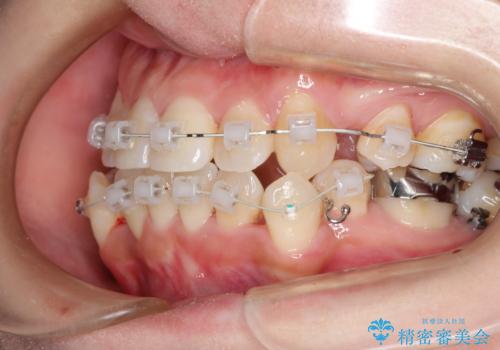

- 矯正装置

- 審美装置(ブラケット:白/ワイヤー:白)

スペースの不足量が著しく、上下左右の抜歯を伴うワイヤー矯正にて治療を行いました。

抜歯によるスペースを利用し、強いがたつきの改善を行いました。

また、左上の奥歯に関して親知らずの1つ手前の歯の状態が悪かったため、その歯は抜歯をし親知らずを利用して噛み合わせを作りました。